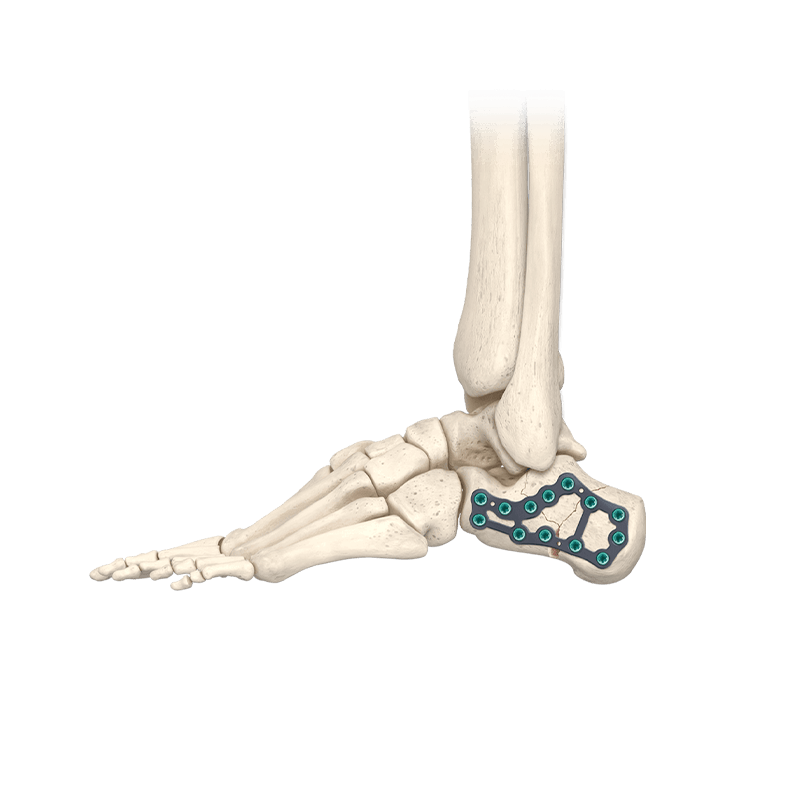

CoLink® Cfx Calcaneal Fixation System

Four plate families to address traumatic fractures and osteotomies of the calcaneus